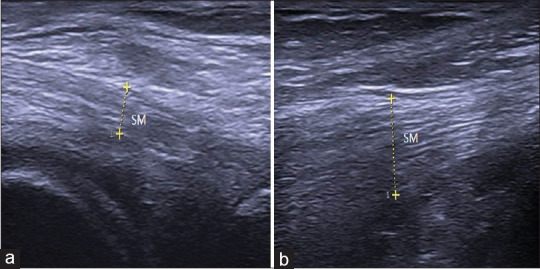

Methods: We studied the distal medial hamstring tendons (semimembranosus [SM] and semitendinosus [ST]) of 104 patients (104 knees) with nontraumatic unilateral PM knee pain and 118 healthy controls (236 knees). U/S evaluations included tendon thickness, echogenicity, the presence of intrasubstance tears, calcifications, and vascularity.

Results: The mean age of patients and controls was 51.7 ± 10.4 years and 49.8 ± 9.9 years, respectively. The mean Visual Analog Scale (VAS) for pain among patients was 5.1, with 58.6% of them reporting pain at the medial joint line. The study patients had significantly higher mean SM and ST tendon thicknesses than the controls (7.17 mm vs. 5.46 mm and 3.93 mm vs. 3.45 mm, respectively). U/S abnormalities among patients were hypoechogenicity (62.5%), intrasubstance tears (31.7%), loss of fibrillar pattern (23.1%), baker cyst (20.2%), calcification (18.3%), anserine bursitis (11.5%), and neovascularization (6.7%). We found significant correlations between tendon thickness and VAS (r = 0.752, P = 0.004) as well as pain location (r = 0.680, P = 0.008). SM tendon thickness measured by U/S was more accurate in predicting tendinopathy than ST (80.6% vs. 68.9%).